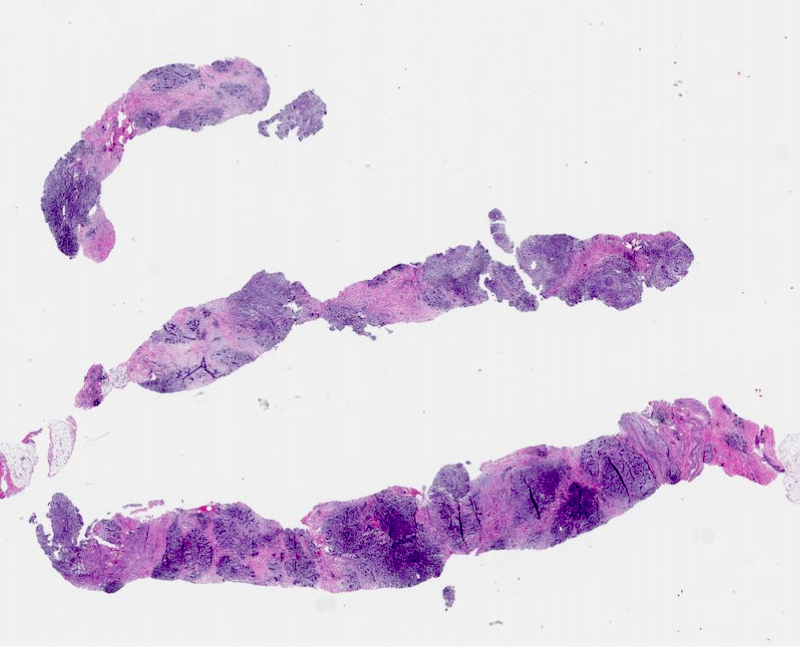

Microscopic (histologic) images